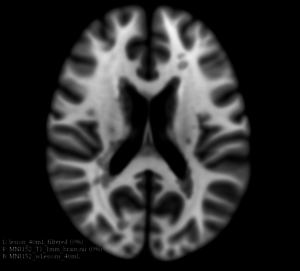

This extension offers a set of tools for brain lesion simulation, based on MRI images. At the moment, the module MS Lesion Simulator is available, where it can simulate both baseline scan lesion volumes (given a lesion load) and longitudinal image simulations. In summary, a statistical lesion database is generated based on a set of manual lesion mark-ups, being non-linearly registered to MNI152 space (isotropic 1mm of voxel resolution), and a local contrast ratio is applied on each imaging modality provided by the user. Using a small set of parameters (lesion load, lesion homogeneity, lesion intensity independence and lesion variability), it is possible to generate a broad range of MS lesions patterns in multimodal MRI imaging techniques (at moment, T1, T2, T2-FLAIR, PD, DTI-FA and DTI-ADC images are provided). For more details about this project, please see the original paper.